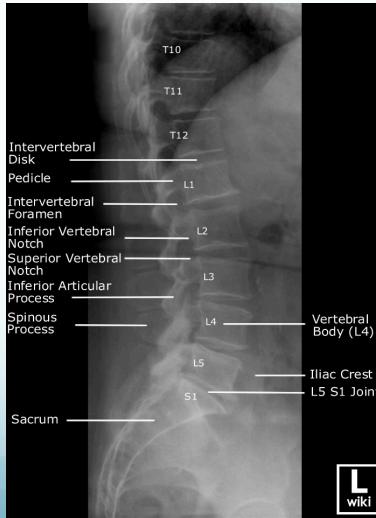

Radiographic (X-Ray) Views

- Standard Views: AP (Anteroposterior), LAT (Lateral)

Natural Spinal Curves

The spine has 4 natural curves to distribute mechanical stress during movement:

- Cervical: Lordosis (inward curve)

- Thoracic: Kyphosis (outward curve)

- Lumbar: Lordosis (inward curve)

- Sacral: Kyphosis (outward curve)